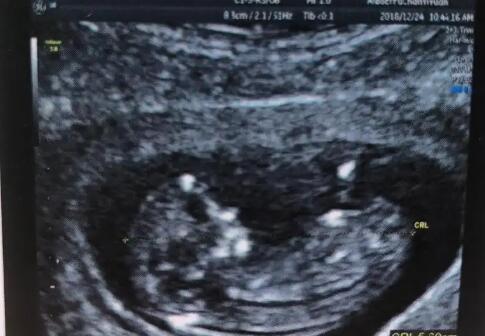

邯鄲市婦幼保健院生殖中心試管嬰兒成功率在40%-51%左右,妊娠率在40%以上。生殖中心建立了輔助生殖實(shí)驗(yàn)室和胚胎培養(yǎng)室,嚴(yán)格按照衛(wèi)生部關(guān)于輔助生殖技術(shù)的規(guī)范要求。近年來(lái),醫(yī)院生殖中心的試管嬰兒周期逐年增加,保持了較高的成功率。以下依據(jù)1顆基礎(chǔ)卵泡數(shù)量預(yù)測(cè)到邯鄲婦幼保健院做試管成功率,可參考下表: